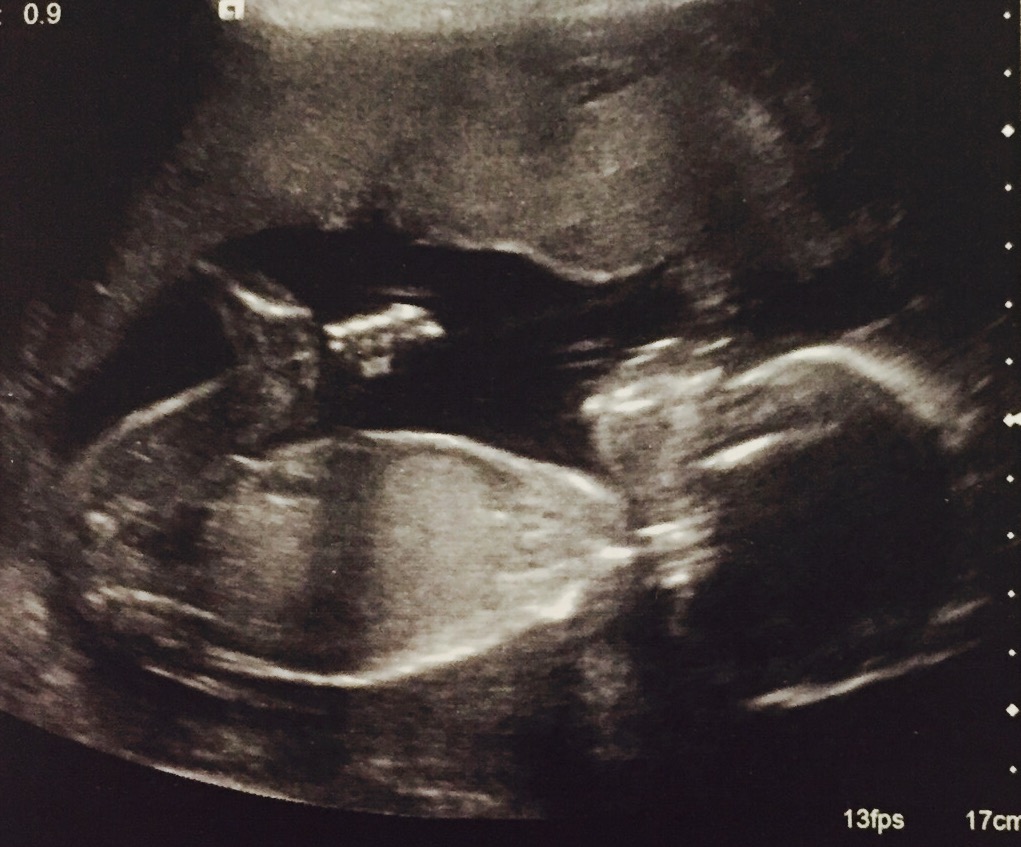

20+5 week scansAttachment 35790Attachment 35791Attachment 35792